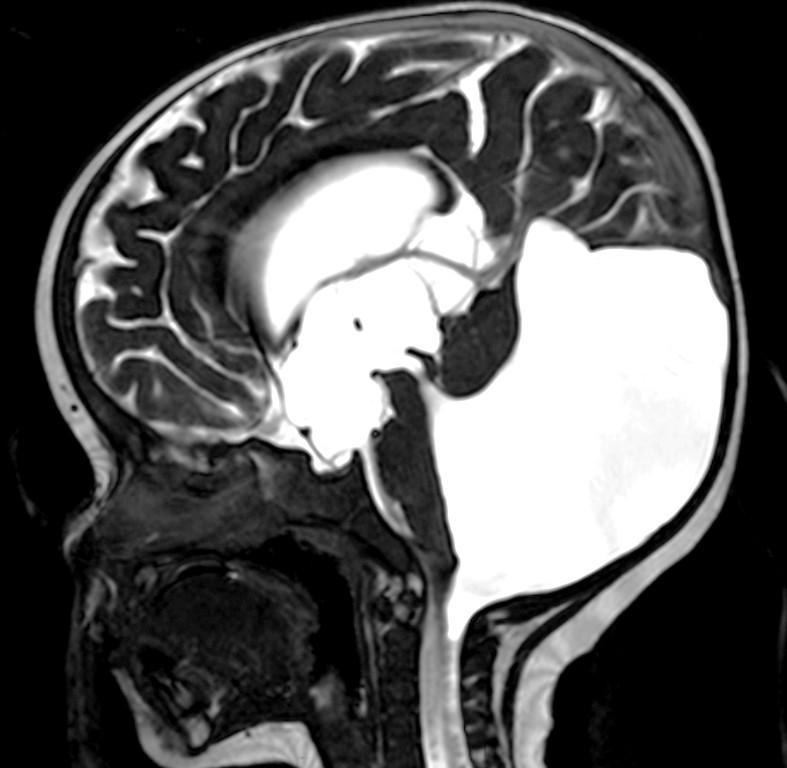

Alobar

Most severe, complete lack of “cleavage”, fused thalami.

Semilobar

“ in between” with separated occipital lobes

Lobar Mild, often only anterior frontal lobe fused, with separate thalami